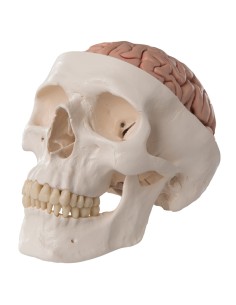

Dal cranio in 22 parti con incastri magnetici ai modelli di colonna vertebrale, da quelli di articolazioni a quelli di cuore, ogni pezzo della nostra collezione è progettato per un’immersione totale nello studio dell’anatomia umana. I nostri modelli, realizzati tramite scansioni di ossa vere, garantiscono un’esperienza tattile autentica e una fedeltà di peso quasi identica agli originali.

Essenziali per studenti e professionisti, i nostri modelli anatomici sono strumenti didattici che permettono di osservare le strutture anatomiche con precisione, eliminando la necessità di dissezioni o studi invasivi. Sono inoltre utili per spiegare ai pazienti le patologie, rendendo la comunicazione più efficace e risparmiando tempo prezioso.